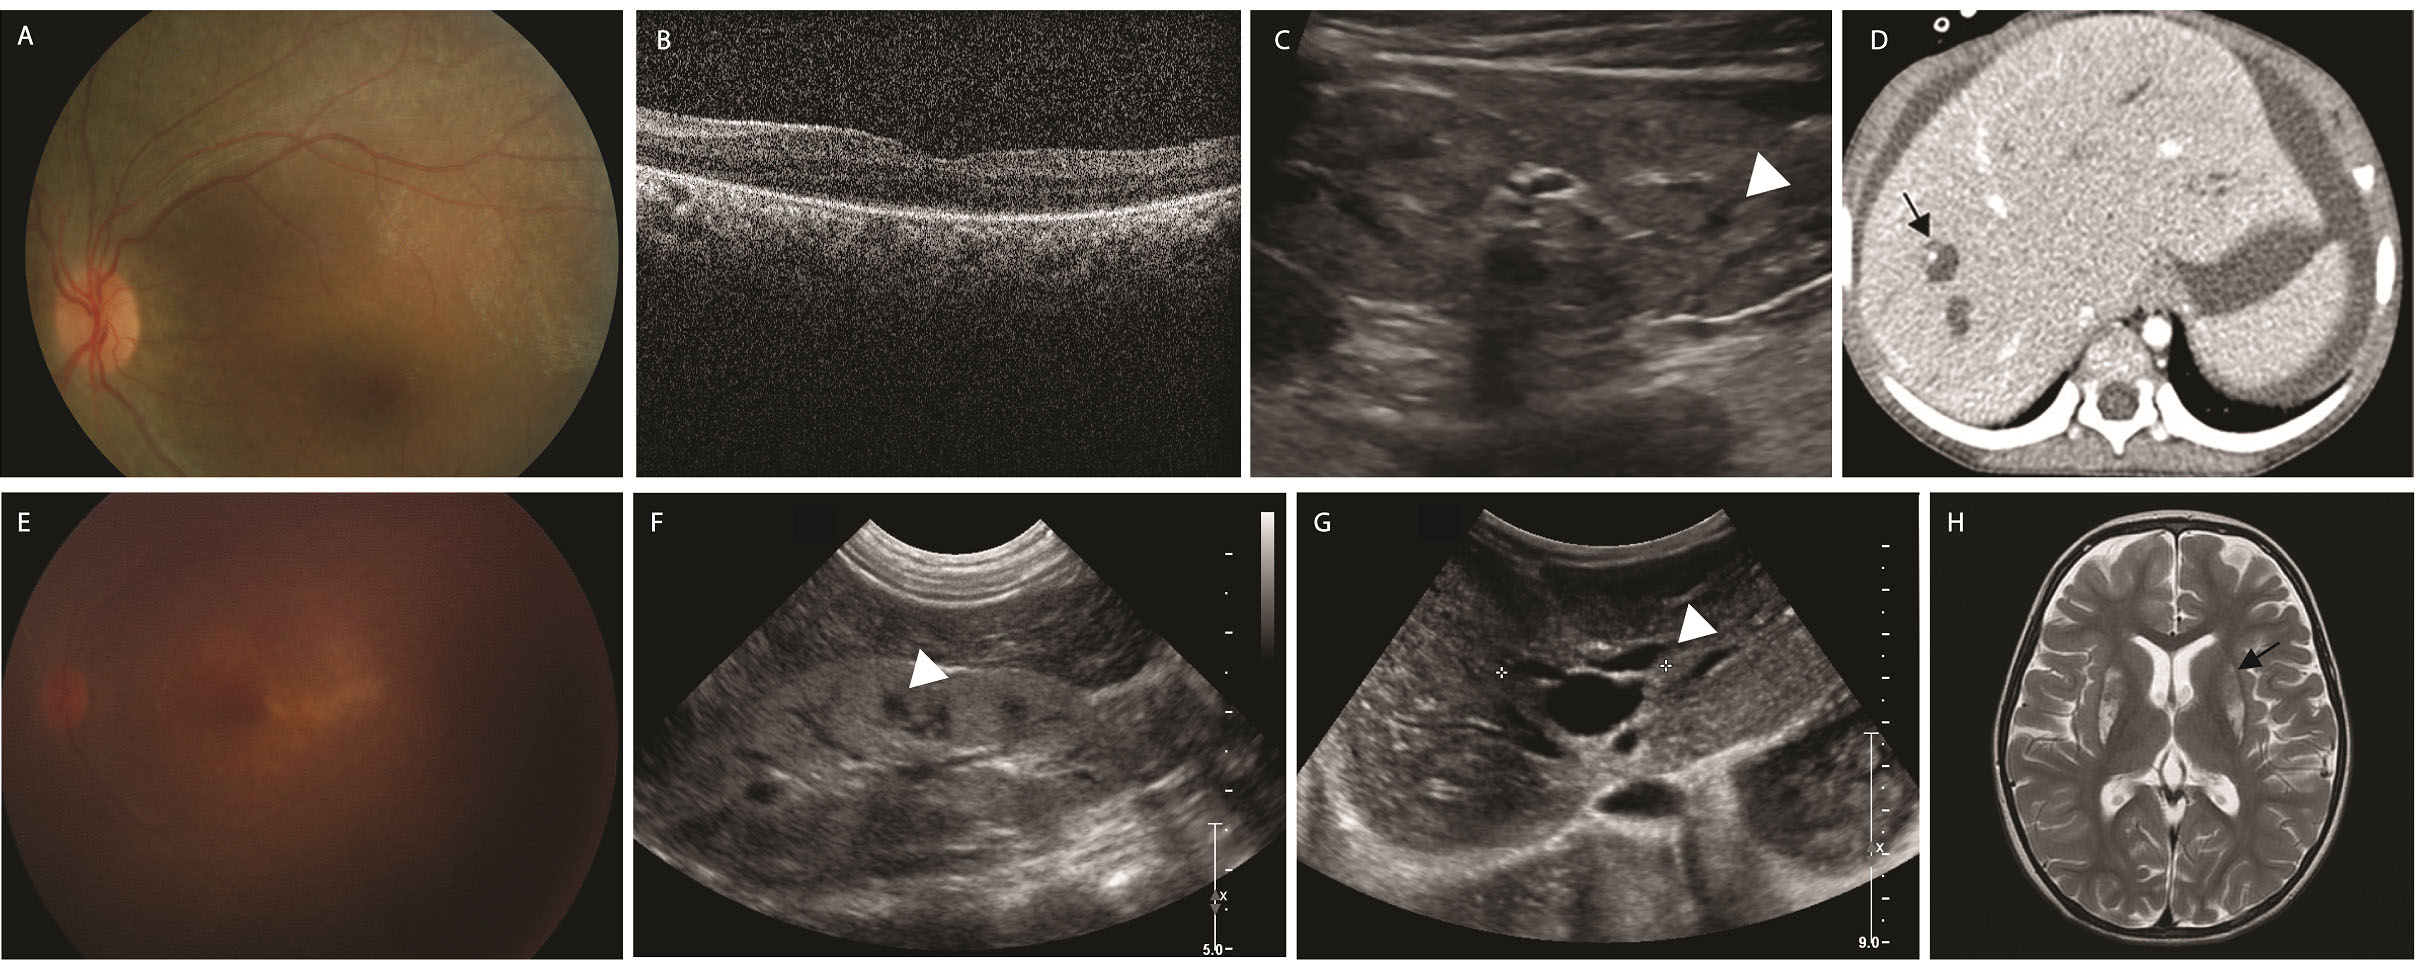

Figure 2. Two patients with nephronophthisis and Caroli disease with homozygous mutations in WDR19 c.3533G>A. A–D: Fundus photograph, optical coherence tomography, renal ultrasonography, and abdominal computed tomography of a 7-year-old

patient with Leber congenital amaurosis (LCA) with a homozygous mutation in WDR19 c.3533G>A (P36). Increased kidney echogenicity, multiple cystic formation of the kidney, and dilated intrahepatic bile duct

were noted. She was neurologically normal. E–H: Fundus photograph, renal and abdominal ultrasonography, and brain magnetic resonance imaging (MRI) image of a 4-year-old

patient with possible dual diagnosis of mutations in WDR19/POLG (P37). Brain MRI showed a bilateral T2 hyperintense signal in the putamen, which was not reported in Senior-Løken syndrome

(black arrow). These findings suggest a possible dual diagnosis.